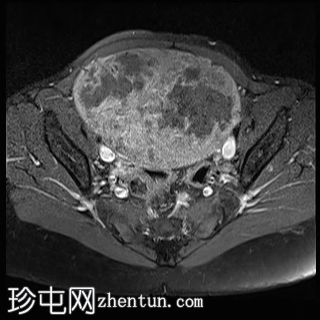

2.jpg

轴向T1

脂肪饱和度

子宫后壁可见一个边界清晰、体积较大的浆膜下肌瘤,大小约为16.1 x 10.5 x 14.4 cm(宽 x 深 x 高)。

该肌瘤在T1加权像上呈中等信号,在T2加权像上呈低信号,内部区域呈囊性变性。

该肿块导致正常子宫结构严重变形。增强扫描显示轻度不均匀强化,未见弥散受限征象或提示恶性肿瘤的可疑强化。